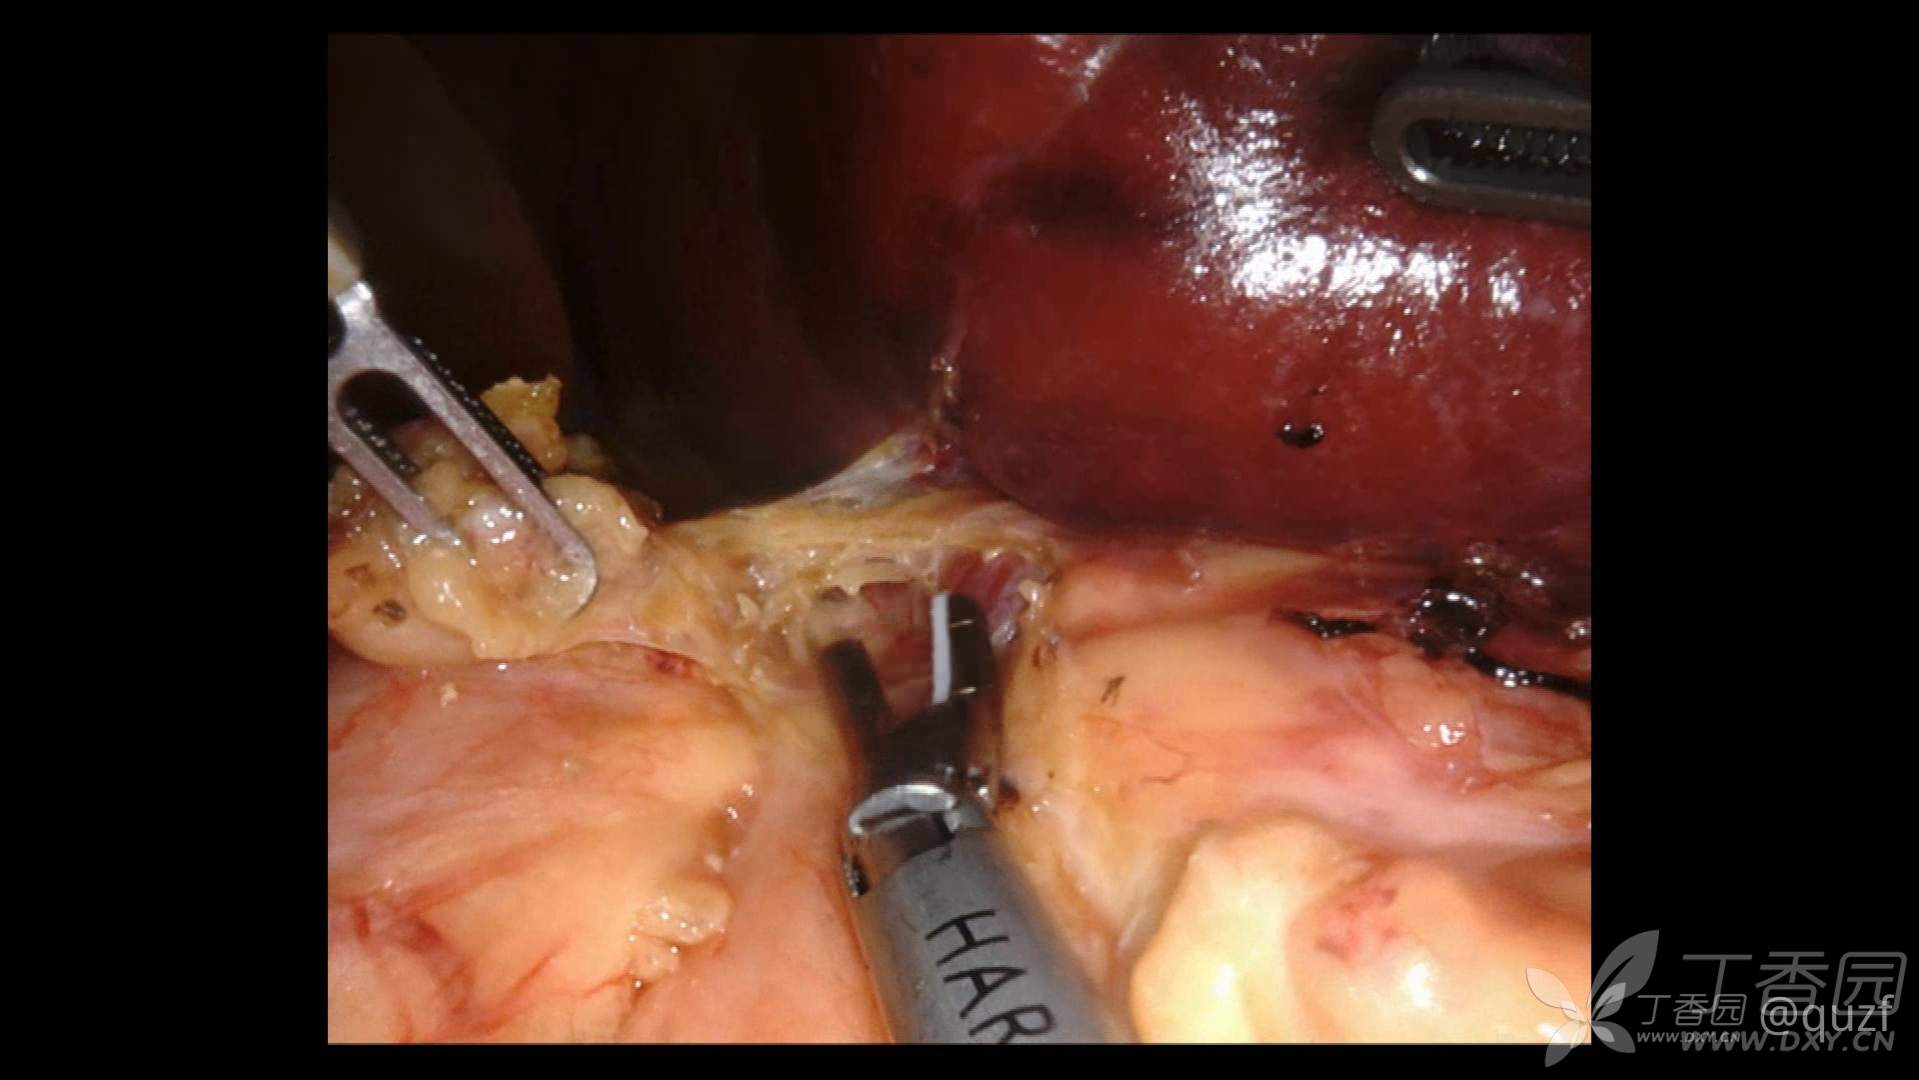

7月7日,我们决定在达芬奇机器人的援助下给孩子做脾脏切除手术,此前我们已经完成机器人辅助下食管裂孔疝修补,胆总管囊肿切除,肾盂输尿管狭窄等一系列复杂手术,但这是我们做的第一例机器人巨脾切除术,术前还是做好了充分准备,用时3个多小时顺利完成了手术。

和以前的传统腹腔镜手术相比“达芬奇”确实有了很多优势。达芬奇机器人的机械臂虽然略显庞大,但是其前端的机械手臂却更加灵活、精细、精巧,活动幅度和范围较手工操作更加广泛,旋转动作不疲劳,更加平顺、稳定,尤其其自动滤除人体颤抖功能,在重建、缝合过程中,可消除人体疲劳或者肢体抖动带来的误差,更加精准的重建器官功能,同时减少副损伤。患儿年龄越小,术区空间愈小,其机器人机械瘦手臂的灵活性更能发挥的淋漓尽致,只要在气腹建立后,各个手臂可以建立安全穿刺范围,手术即可进行。另外,机器人主刀不但是操作者,也是镜头控制者,可按照术者的思路观察手术区域;因患儿操作空间小,传统的腹腔镜操作对扶镜助手是巨大的考验,轻微的晃动即可影响主刀视野,严重影响主刀操作,但机器人可以规避这一弊端,机器人手术真正达到了体表的微创和术区的微创!